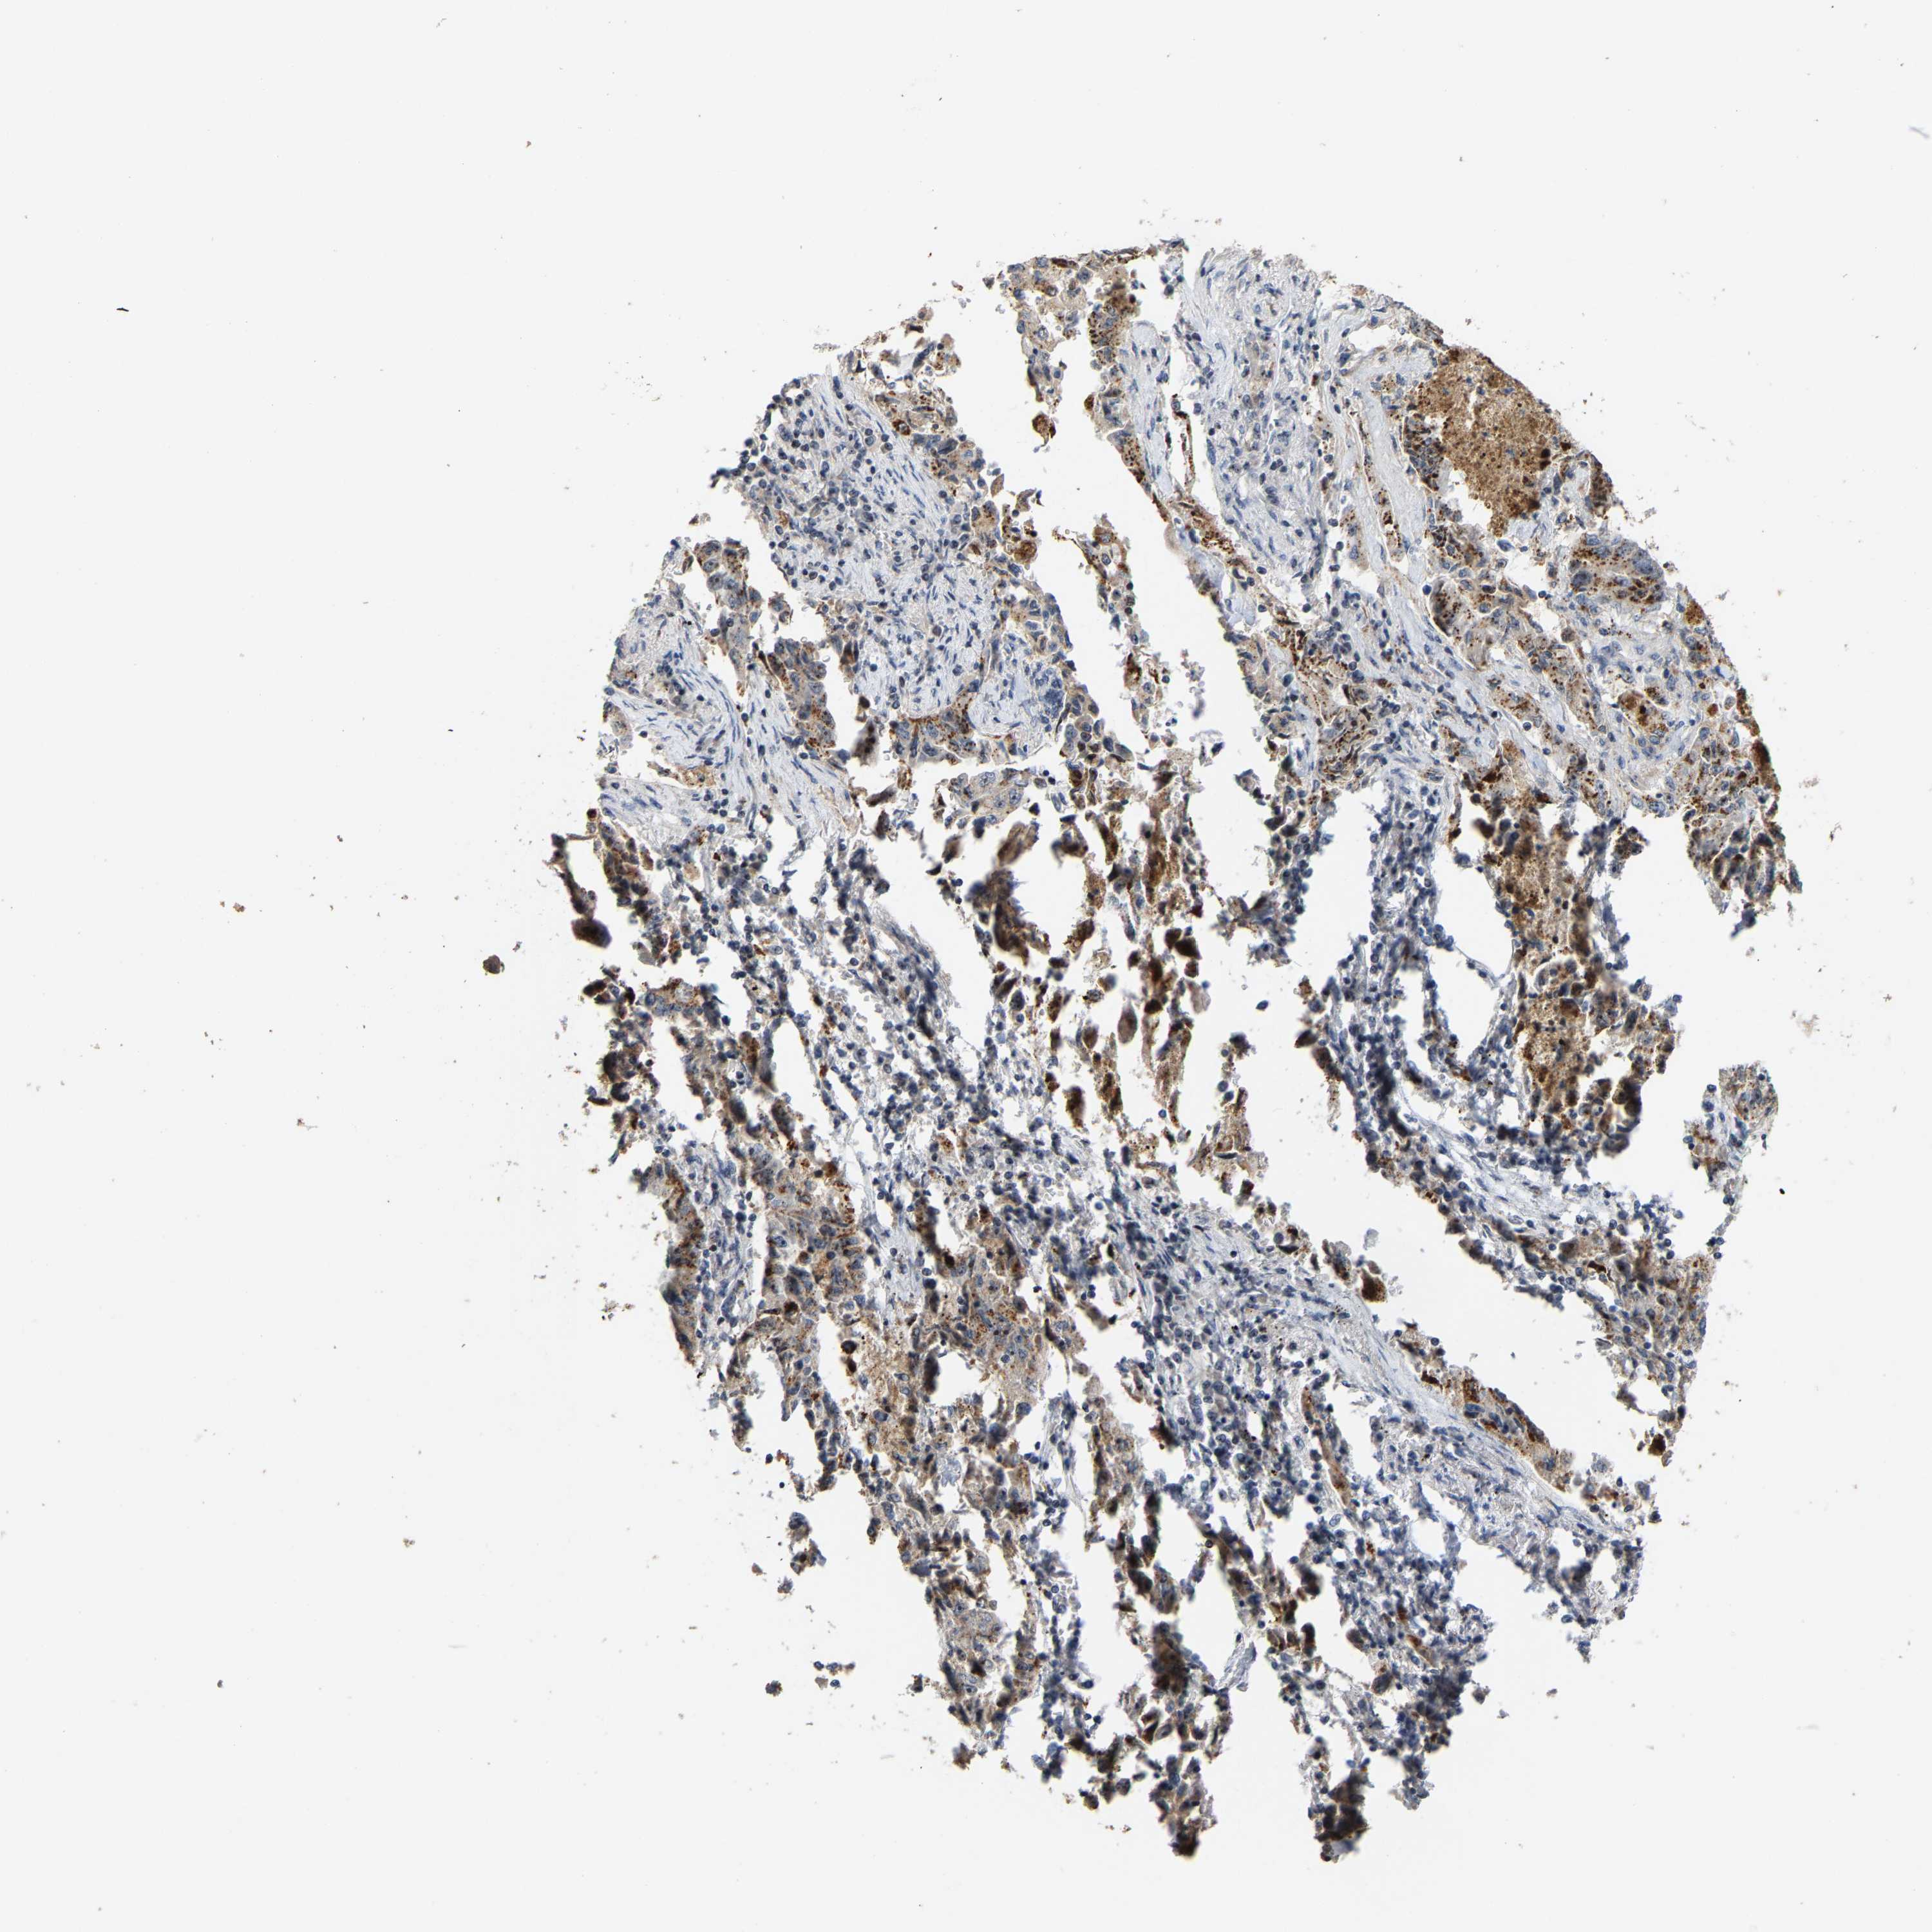

LUNG ADENOCARCINOMA (TCGA) - Interactive survival scatter ploti

The Survival Scatter plot shows the clinical status (i.e. dead or alive) for all individuals in the patient cohort, based on the same data that underlies the corresponding Kaplan-Meier plots. Patients that are alive at last time for follow-up are shown in blue and patients who have died during the study are shown in red.

The x-axis shows the expression levels (FPKM) of the investigated gene in the tumor tissue at the time of diagnosis. The y-axis shows the follow-up time after diagnosis (years). Both axes are complimented with kernel density curves demonstrating the data density over the axes. The top density plot shows the expression levels (FPKM) distribution among dead (red) and alive patients (blue). The right density plot shows the data density of the survived years of dead patients with high and low expression levels respectively, stratified using the cutoff indicated by the vertical dashed line through the Survival Scatter plot. This cutoff is automatically defined based on the FPKM cutoff that minimizes the p-score. The cutoff can be changed by dragging the vertical line or by entering a cutoff value in the square labeled "Current cut-off".

Under the Survival Scatter plot the p-score landscape (black curve; left axis) is shown together with dead median separation (red curve; right axis). Dead median separation is the difference in median mRNA expression between patients who have died with high and low expression, respectively. It is calculated as follows: median FPKM expression of dead patients with high expression - median FPKM expression of dead patients with low expression. This is intended to aid the user in visually exploring custom cutoffs and the associated p-scores and dead median separation.

Individual patient data is displayed and can be filtered by clicking on one or more of the category buttons on the top of the page. Categories describing expression level and patient information include: high, low, alive, dead, female, male and tumor stages. The scale of the x-axis can be toggled between linear and log-scale by clicking on the "x log" button. Mouse-over function shows TCGA ID, patient information and mRNA expression (FPKM) for each patient.

& Survival analysisi

Kaplan-Meier plots summarize results from analysis of correlation between mRNA expression level and patient survival. Patients were divided based on level of expression into one of the two groups "low" (under cut off) or "high" (over cut off). X-axis shows time for survival (years) and y-axis shows the probability of survival, where 1.0 corresponds to 100 percent.

NOP58 is not prognostic in Lung Adenocarcinoma (TCGA)

: 55.44

P scorei

N/A

Average pTPM 51.0

Number of samples 497